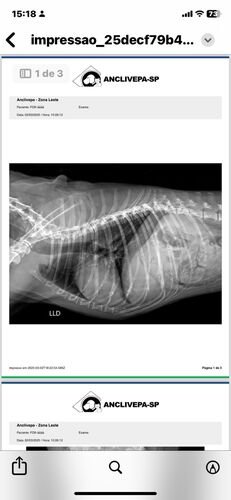

No dia 02 de março de 2025, Fox sofreu um grave acidente. Uma linha de pipa com cerol passou pela laje de casa e cortou a Fox. Assustada, ela caiu da laje de uma altura de 3 metros, sofrendo diversas fraturas nas patinhas e costelas, lesões internas que prejudicaram sua mobilidade.